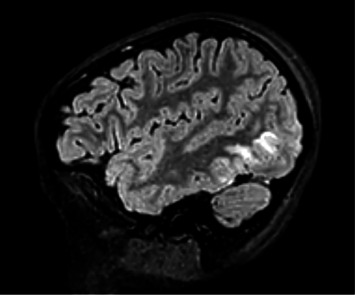

History: An 8-year-old previously healthy female presented to the emergency department after new-onset seizure activity. Three days prior, she experienced severe headaches and rash over her left lower extremity. She developed nonbilious, nonbloody emesis on the day prior to admission. The morning of presentation, she was found unresponsive, exhibiting right gaze deviation and clenched jaw concerning for seizure activity. Further history revealed recent Group A streptococcal pharyngitis, which had been treated with a 10-day regimen of amoxicillin. During this time, her mother reported decreased oral intake but normal urinary output, without dysuria or hematuria. Physical Examination: Vital signs were notable for temperature of 101.7 degrees Fahrenheit, heart rate of 100 beats per minute, blood pressure of 167/97, respiratory rate of 28, and oxygen saturation of 96% on room air. The patient was drowsy but arousable. Her neck was supple without evidence of meningismus. A skin exam revealed an erythematous, crusting rash, resembling contact dermatitis on the left lower extremity below the knee. The patient was somnolent but oriented to self and able to follow simple commands. Cranial nerves II-XII were intact bilaterally. Sensory, motor, and coordination were unremarkable. Laboratory, Imaging, and Procedures: Laboratory findings included leukocytosis, microscopic hematuria, decreased C3 and C4 levels, and positive antistreptolysin O (ASO) titers. A lumbar puncture was conducted with unremarkable cerebrospinal fluid (CSF) indices. Imaging revealed hypoattenuation in the occipital lobes on computed tomography (CT) venogram and hyperintensities in bilateral occipital lobes on magnetic resonance imaging (MRI) T2 fluid-attenuated inversion recovery (FLAIR) sequences, consistent with posterior reversible encephalopathy syndrome (PRES). Discussion: PRES in pediatric patients has been associated with a variety of conditions including hypertension (idiopathic or secondary), renal disorders, autoimmune disorders, and hematologic or oncologic conditions. However, PRES secondary to acute postinfectious glomerulonephritis (PIGN) is rare. Hematuria on the urinalysis led to obtaining complement levels, and further elucidation of history helped to narrow the differential to PIGN due to streptococcal infection with confirmatory positive ASO antibody titer. This case highlights a rare sequala of a commonly seen pediatric infection.